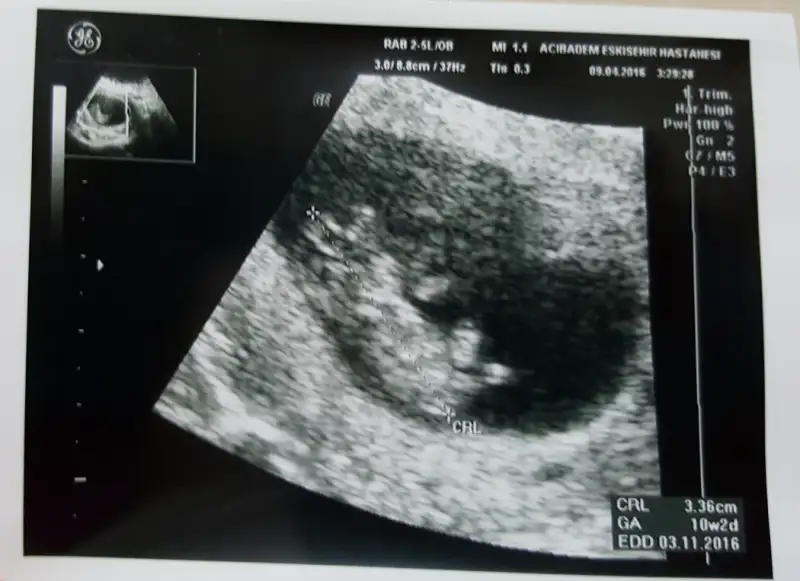

anlayan arkadaşlar bana da yorum yaparmsnz??karindan usg

hala erkek mi dusunceniz? 10+2 gunluguz :))